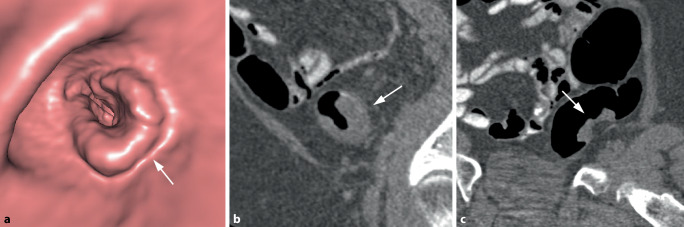

Abstract Image